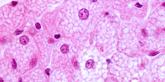

As adipose tissue expands, it becomes a hotbed of immune activity, attracting macrophages, key immune cells that adapt to their surrounding environment. In lean individuals, most macrophages in adipose tissue exhibit an anti-inflammatory M2 phenotype, functioning like maintenance workers that support tissue repair and balance. However, in obesity, macrophages shift toward a pro-inflammatory M1 phenotype, acting more like alarm responders. These activated M1 macrophages release additional cytokines, including tumor necrosis factor-alpha (TNF-α) and monocyte chemoattractant protein-1 (MCP-1), which recruits even more immune cells. This infiltration sets off a feed-forward loop of inflammation, progressively worsening local tissue dysfunction and contributing to systemic metabolic disturbances. [2]